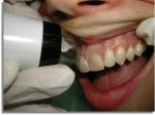

Material/Methods: The study enrolled 80 subjects: 40 subjects with a diagnosis of diabetes mellitus type II (18 males and 22 females, between 44 and 85 years of age); and 40 healthy subjects (17 males and 23 females, between 44 and 78 years of age). All the subjects, both diabetic and healthy, were submitted to a videocapillaroscopic examination of the mucosa of the oral cavity.